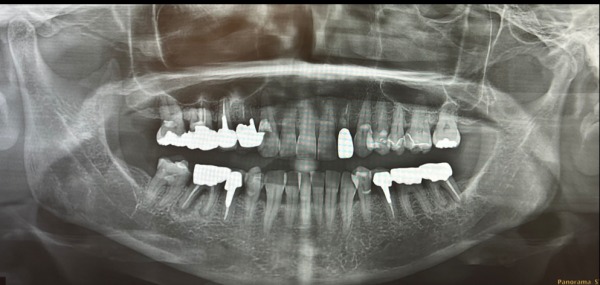

パノラマエックス線撮影と主訴である右下の口腔内エックス線撮影を行いました。

1日目 パノラマエックス線検査、虫歯の有無の確認、歯周病の検査を行いました。

センター南デンタルクリニックでは、初診時に、パノラマエックス線検査と歯周病の検査(歯周ポケットの深さ、歯の揺れ、歯垢の付着度合い)を実施しています。検査結果を聞いていただき、歯垢や歯石の除去(細菌を減らす)を行います。

パノラマエックス線検査は、エックス線の透過度の違いにより、歯や骨といった硬組織が白く映ります。エックス線の透過性から骨の形を知ることができます。